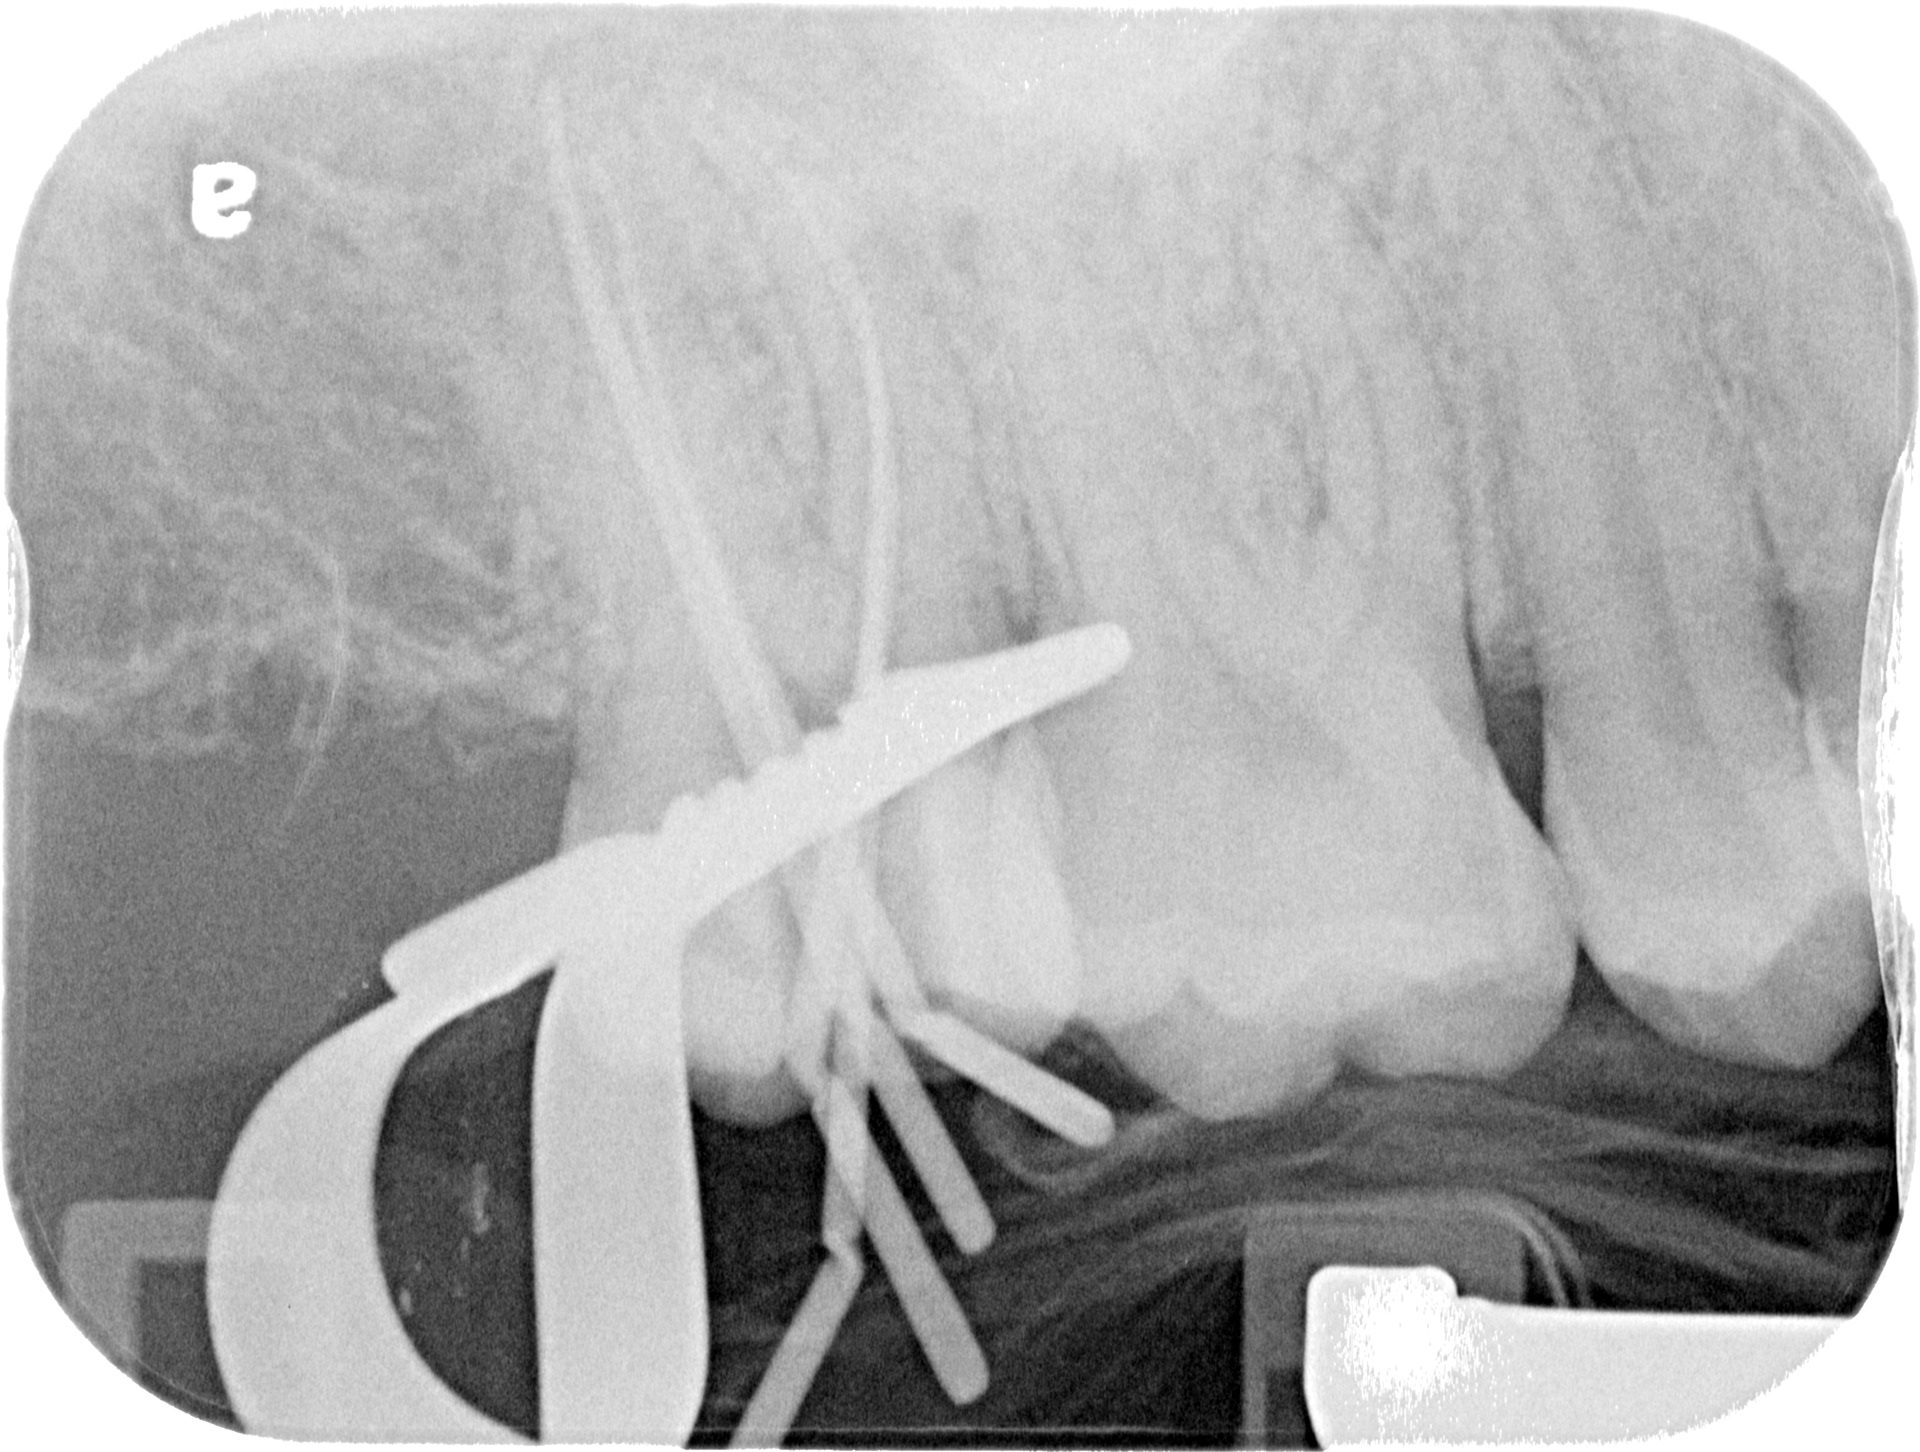

CURVES...

BEFORE

AFTER